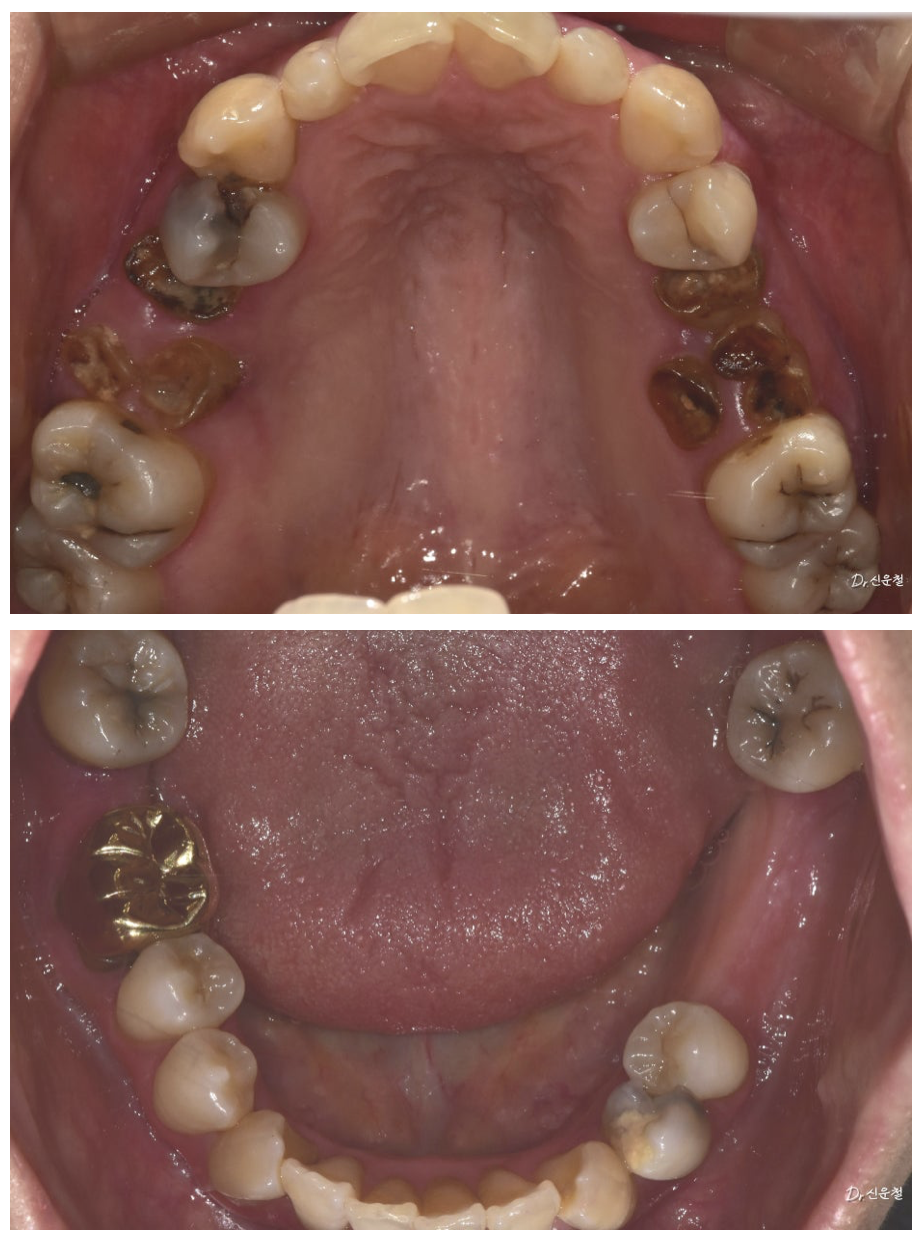

앞니만이 아니라 ‘웃는 전체’를 보셔야 합니다

많은 분들이 이렇게 말씀하십니다.

“앞니만 조금 정리하면 될 것 같아요.”

웃을 때는 앞니만 보이지 않습니다.

어금니까지 함께 보입니다.

앞니 배열만이 아니라 어금니 충치, 보철 색감, 잇몸 라인까지

전체적인 밸런스를 함께 봐야 합니다.